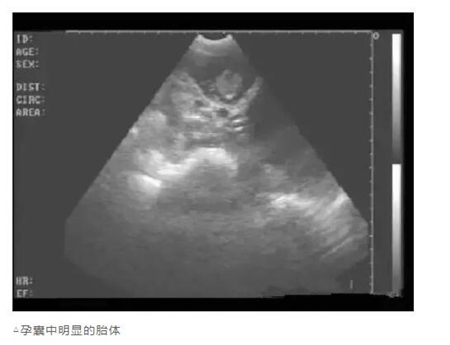

用B超检查母猪妊娠情况,怎样根据显示的图像辨别妊娠状态呢?详细的图文教学分享给大家!